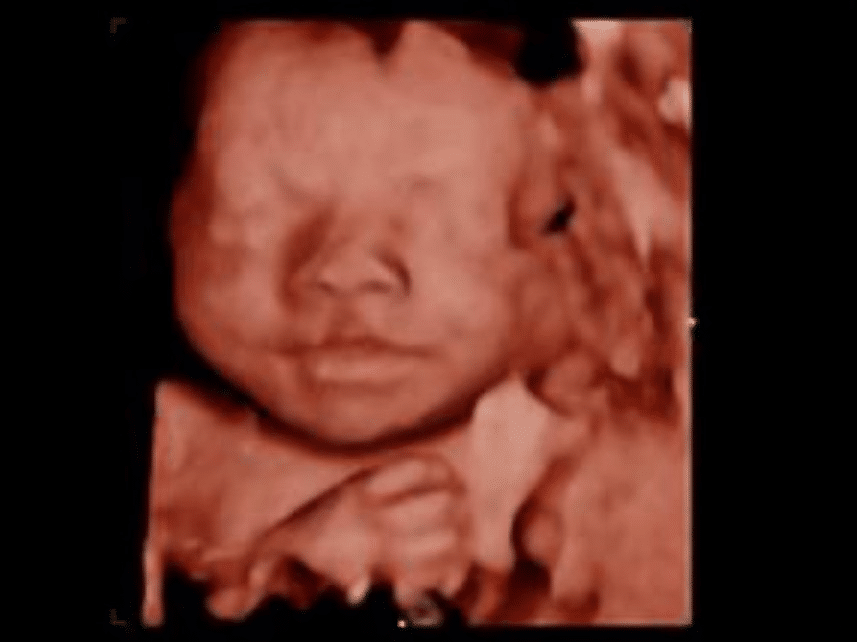

Baby Girl photo

Baby Girl

In May, 2023 we received an exciting call saying we have been matched with a birth mom. For the next five months we continued to fund raise, prepare our house, lives, and our community for the arrival of this sweet girl. We were fortunate to meet the birth mom and have built a relationship with her. We can not wait to bring this sweet baby girl home to join our family.